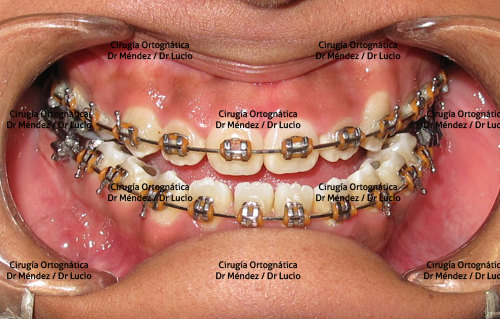

HIPOPLASIA MAXILAR Paciente operado de avance maxilar |

||